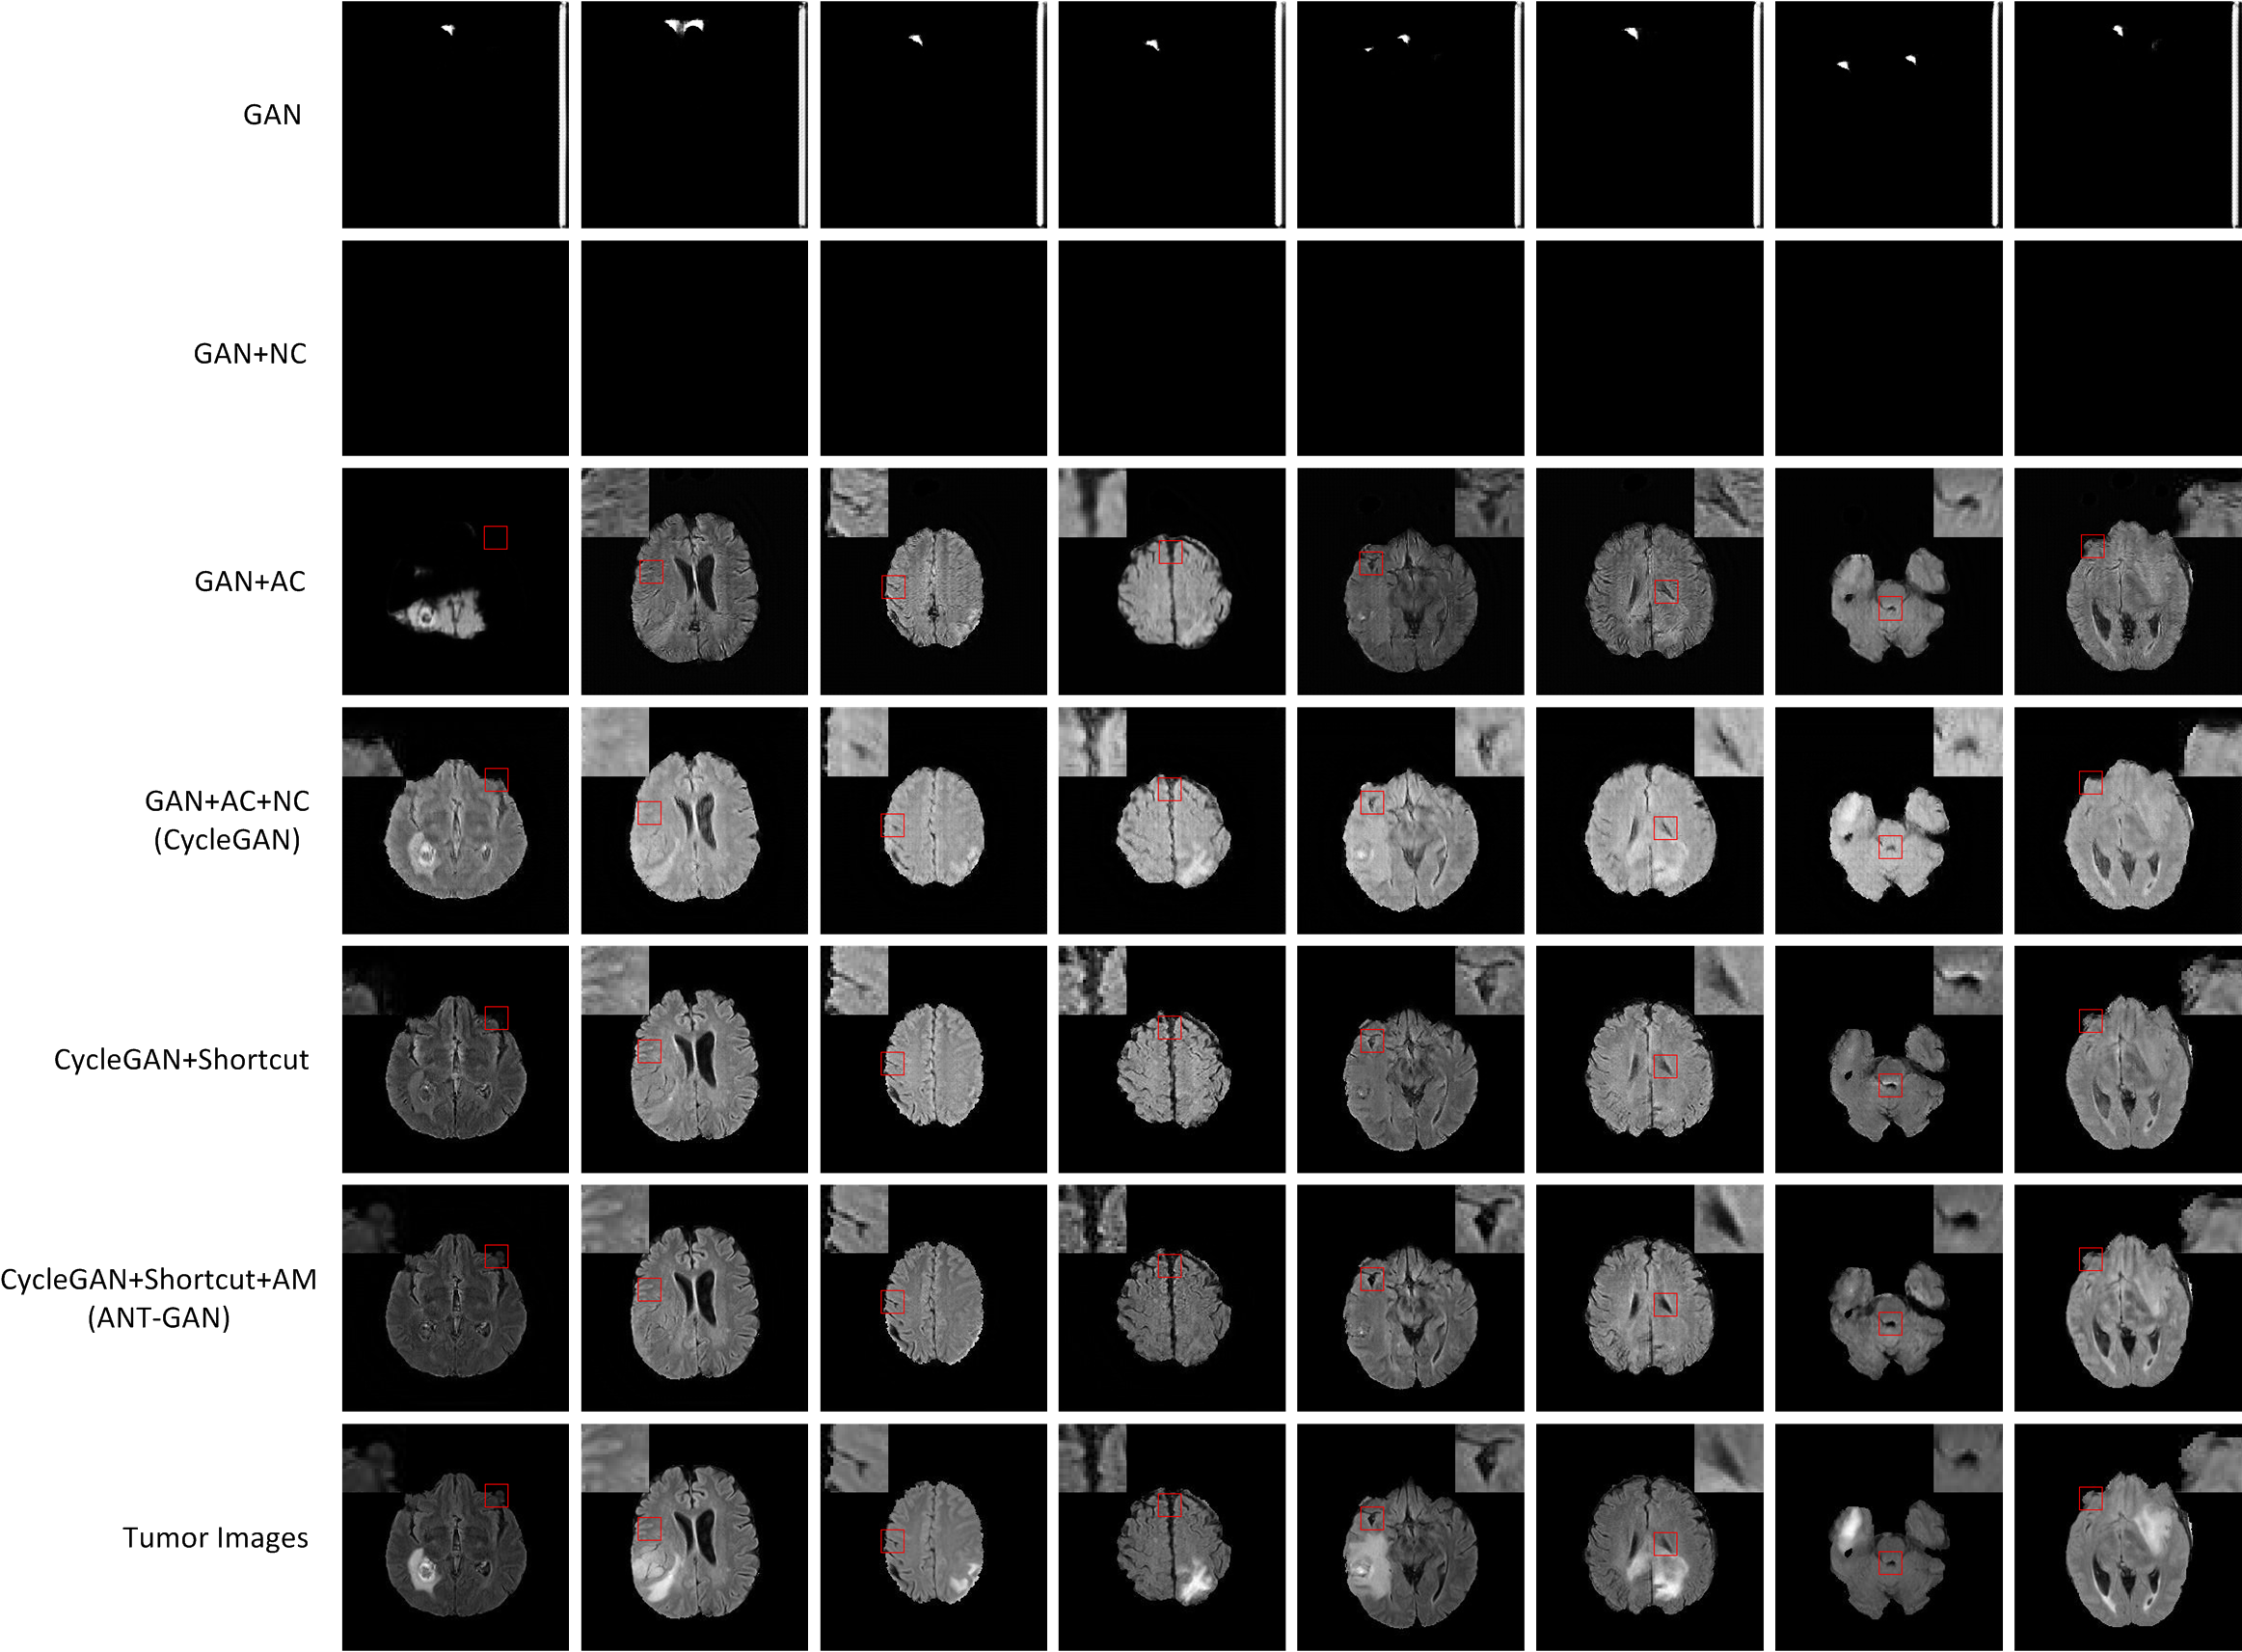

We use two popular medical imaging datasets primarily used for the evaluation of lesion segmentation: the Multimodal Brain Tumor Segmentation Challenge 2018 dataset (BratS18) [21, 2] and the Liver Tumor Segmentation Challenge dataset (LiTS).

BratS18.

The BratS18 dataset provides 210 high grade glioma (HGG) and 75 lower grade glioma (LGG) MRI with binary masks for the tumor (or lack of tumor). Each 3D MRI contains 155 slices of size 240×240240240240\times 240. Not every slice contains a tumor, and therefore healthy MRI are provided by this data as well. We use the FLAIR modality image for all the experiments because the entire tumor is represented well by this modality.However, we also show more experimental results on other modalities, where the ANT-GAN provides impressive visual quality. A more detailed medical description of the data can be found on the challenge website.111https://www.med.upenn.edu/sbia/brats2018.html

LiTS.

We also experiment with the LiTS data containing a total of 131 contrast enhanced abdominal CT volume images of the liver acquired from 7 different clinical institutions. The in-plane resolution ranges from 0.5mm to 1mm and the slice thickness ranges from 0.7mm to 5.0mm. Each slice is 512×512512512512\times 512 in size and we resize them to 256×256256256256\times 256, and as with the BratS18 MRI not every slice contains a lesion and so these slices are considered to be healthy images. A detailed data description can be found on the challenge website. 222https://competitions.codalab.org/competitions/17094

Aside from the difference in imaging tissue and modality of these two data sets, the tumor regions on the CT images are of different shape and size, as can be seen in Figure 4. Also, many CT scans are acquired in a way that introduces greater noise-like artifacts than MRI. For each dataset, 80%percent8080\% of randomly selected data are used for training and the resting 20%percent2020\% for testing.